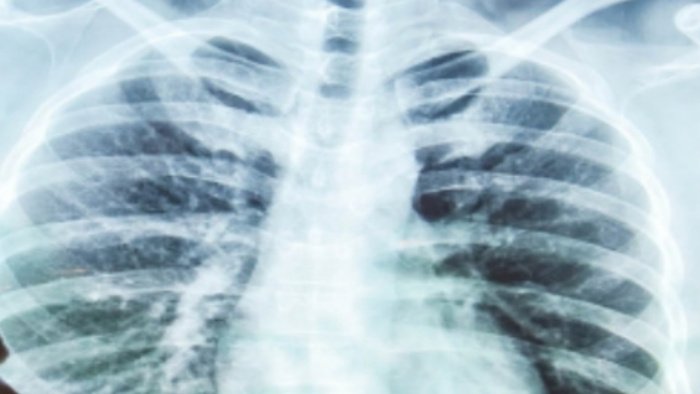

WAWAINEWS.ID – Sindrom gangguan pernapasan akut atau paru-paru basah adalah salah satu keadaan darurat medis yang berpotensi mengancam jiwa jika tidak ditangani dengan maksimal.

Ketika kantung udara di paru-paru (alveoli) dipenuhi dengan cairan, bukan udara bisa disebut sebagai paru-paru basah mulai mendera.

Karena jika cairan di paru-paru terlalu banyak menyebabkan penurunan jumlah oksigen atau peningkatan jumlah karbon dioksida dalam aliran darah manusia.

Organ-organ vital lain ikut terdampak tidak bisa menjalankan fungsinya dengan baik, bahkan berpotensi memicu kegagalan organ.

Biasanya cairan yang melekat pada alveoli berupa nanah atau darah akibat efek peradangan atau infeksi virus.